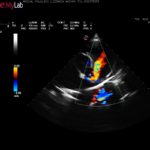

Jest to jedyna wada wrodzona, którą można w pełni skorygować i nie dopuścić, aby w przyszłości u pacjenta rozwinęły się objawy niewydolności krążenia. Jednym z najważniejszych warunków powodzenia operacji jest przeprowadzenie jej w pierwszych miesiącach życia szczeniąt, zanim pojawią się u nich objawy niewydolności serca. Dlatego tak ważne jest w naszej praktyce dokładne osłuchiwanie serca szczeniąt w trakcie badań lekarskich i wczesne rozpoznanie wady. U pacjenta z podejrzeniem wady serca wykonujemy pełne badanie kardiologiczne. Najważniejszym badaniem jest badanie echokardiograficzne z przepływami (badanie dopplerowskie). Innymi badaniami wykorzystywanymi w diagnostyce PDA są RTG klatki piersiowej oraz EKG.

- Widok śródoperacyjny otwartej klatki piersiowej, serca, nerwów oraz dużych naczyń.